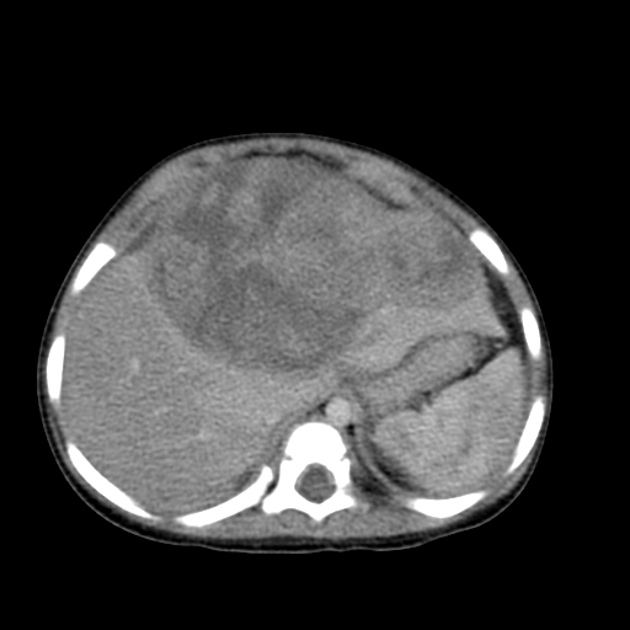

肝母細(xì)胞瘤

日本筑波大學(xué)曾經(jīng)報道過一例質(zhì)子治療的兩歲的晚期肝母細(xì)胞瘤的患兒,在接受了手術(shù)以及化療以后,對殘留的腫瘤給予了輔助的質(zhì)子治療后,患兒的疾病基本得到了控制,12年后仍然無瘤生存。同時,患兒未出現(xiàn)嚴(yán)重副作用,且有效保障了肝功能。